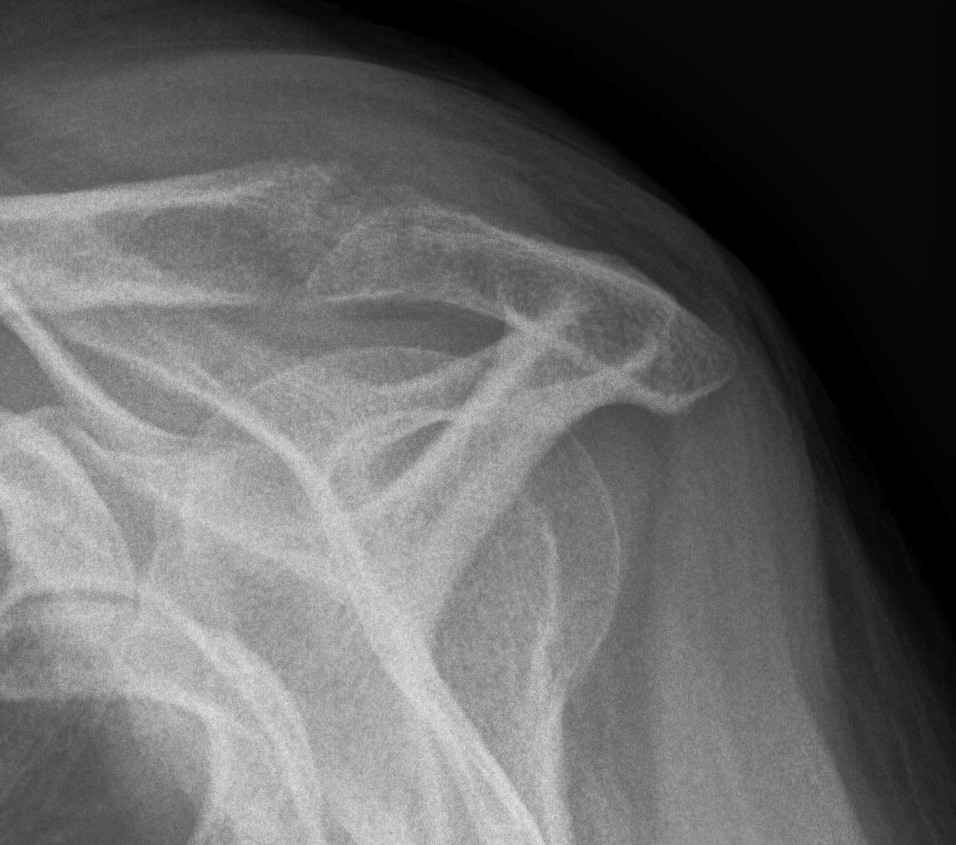

X-ray

| AP | Supraspinatus outlet view | Axillary lateral |

|---|---|---|

|

Sclerosis greater tuberosity / acromion Lateral Acromion spur |

Acromial morphology | Os acromiale |

![]() |